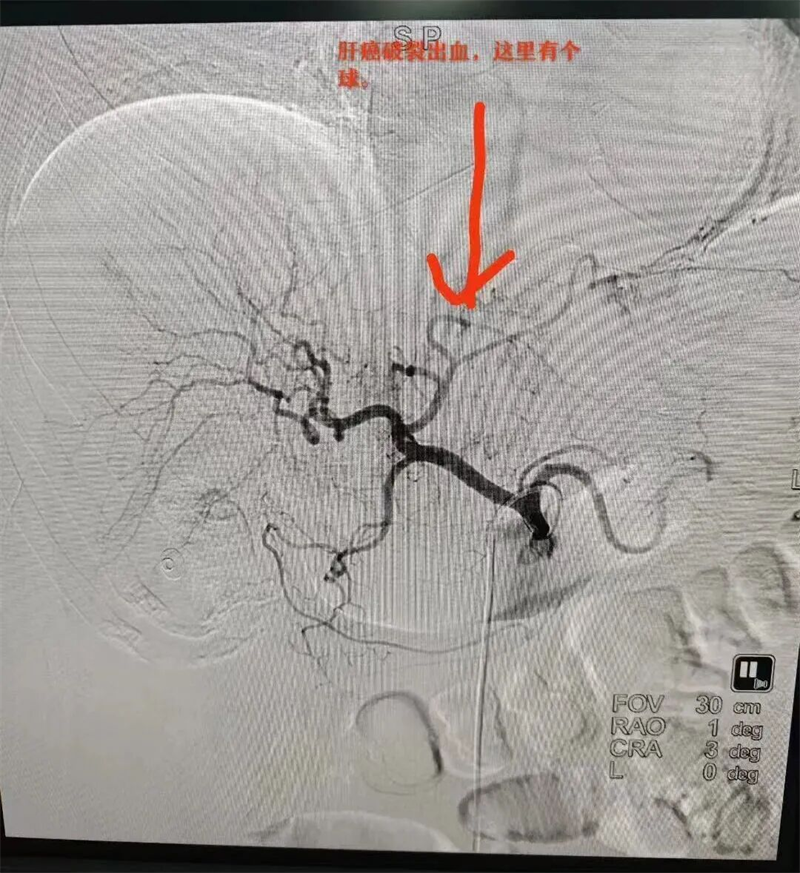

DSA下栓塞前影像

在DSA血管影像引导下,精准找出了出血元凶——肿瘤破裂出血。栓塞后,造影显示肿瘤碘油沉积,出血血管基本看不到,手术达到预期效果。经多学科医护团队后续科学救治及精心护理,患者目前生命体征较平稳,已转出ICU,至普通病房接受后续治疗。